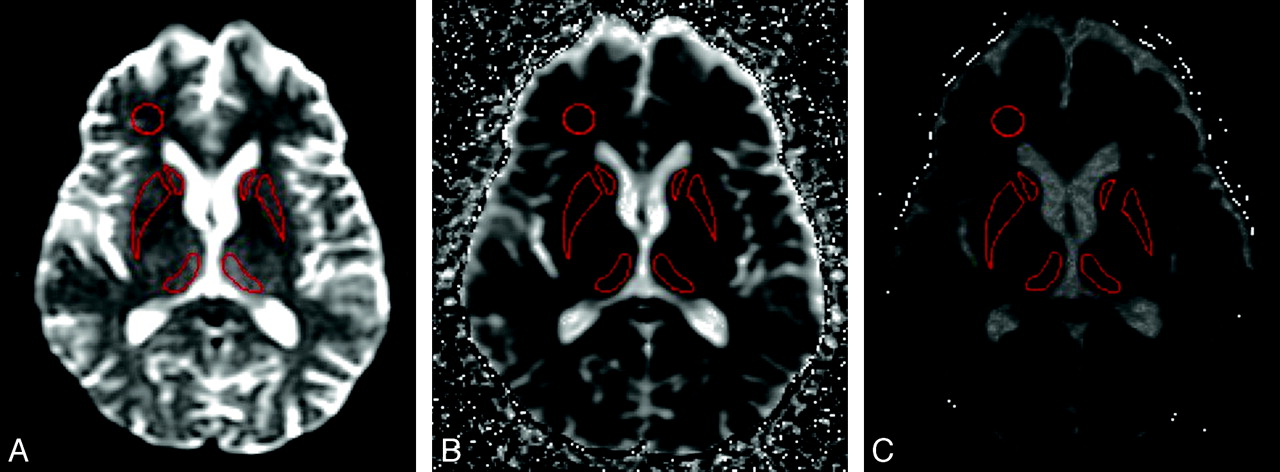

Regional ADC Measurements.

The above ROIs were transferred to the corresponding b = 1000 ADC map (Fig 1) and then to the b = 3000 ADC map, and the mean ADC for each ROI was recorded. For the vCJD cases, mean ROI ADC values in the Pu were also determined. Right versus left asymmetry was also assessed for ADC values in the C, P, Pu, and DM ROIs by using the paired t test, and as no significant asymmetry was detected, the left-right mean ADC values were calculated for these regions. Two control ROIs were selected in the right FWM and the SP. To assess intraobserver variability, the ROI analysis in all 6 regions was repeated for 4 patient datasets in 2 sessions separated by 10 days. Bland-Altman analysis demonstrated a mean difference of −5.1 mm2/s (95% CI = −13.75 to 3.55; P = .235). To assess interobserver variability, a second observer placed ROIs on the same 4 patients and Bland-Altman analysis demonstrated a mean difference of 3.81 mm2/s (95% CI = −5.47–13.08; P = .40).

The position of the key ROIs on (A) b = 0, (B) b = 1000, and (C) b = 3000 ADC map.